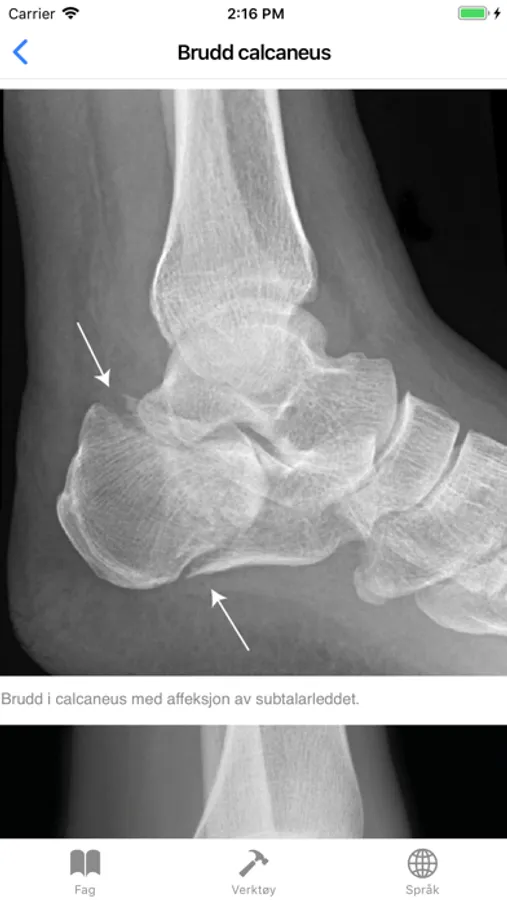

Brudd calcaneus